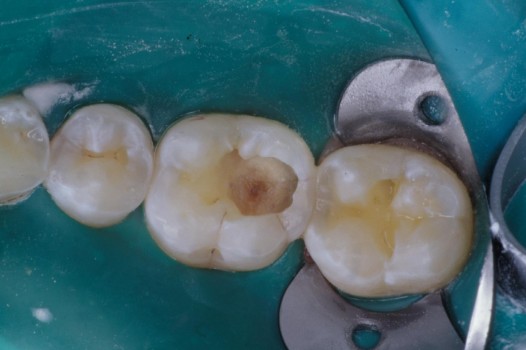

The pits and grooves on the biting surface of teeth often serve as plaque traps and pathways for bacteria to invade the inside of a tooth. This, in turn, leads to the development of cavities. Early diagnosis and treatment arrests the spread of decay and thus prolongs the life of the tooth. Regardless of the size of the affected tooth structure, decay may be swept away with the air abrasion technique and corrected by bonded ceramics, which seal the tooth against further bacterial invasion.